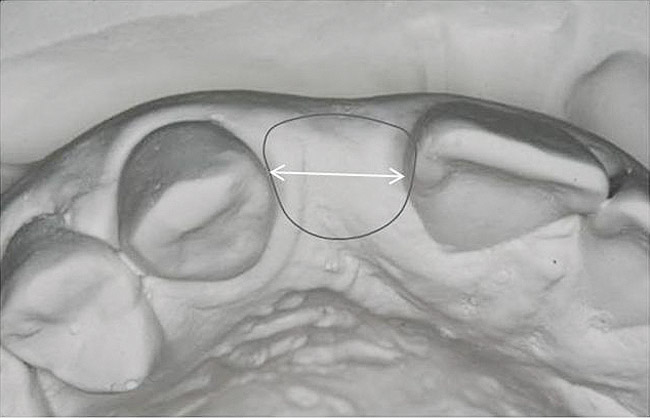

Figure 23  Gingival zenith planning: The location of the gingival zenith for this missing lateral incisor is not fully evident during initial clinical evaluation (Fig 21). Subsequent diagnostic waxing reveals the position of the planned gingival zenith (Fig 22). A thermoplastic template captures the position of the zenith and enables transferring this location to the clinical environment (Fig 23 and Fig 24). Final crown contours are defined by soft-tissue form (Fig 25).

Figure 23

Figure 24  Gingival zenith planning: The location of the gingival zenith for this missing lateral incisor is not fully evident during initial clinical evaluation (Fig 21). Subsequent diagnostic waxing reveals the position of the planned gingival zenith (Fig 22). A thermoplastic template captures the position of the zenith and enables transferring this location to the clinical environment (Fig 23 and Fig 24). Final crown contours are defined by soft-tissue form (Fig 25).

Figure 24

Figure 21   Gingival zenith planning: The location of the gingival zenith for this missing lateral incisor is not fully evident during initial clinical evaluation (Fig 21). Subsequent diagnostic waxing reveals the position of the planned gingival zenith (Fig 22). A thermoplastic template captures the position of the zenith and enables transferring this location to the clinical environment (Fig 23 and Fig 24). Final crown contours are defined by soft-tissue form (Fig 25).

Implant placement according to the 3/2 rule involves using a surgical guide that reveals the location of the gingival zenith. Gingival zenith-oriented planning begins with a diagnostic waxing that identifies the planned tooth contour and related soft-tissue form. This information is transferred to the radiographic assessment and surgical placement using a thermoplastic index that is carefully trimmed to the zenith. In this way, the surgical placement can be monitored and directed from the location of the gingival zenith (Figure 21 through Figure 25). The intended result is placement of the implant/abutment margin 3-mm apical and 2-mm palatal to the clinical landmark. Careful fabrication of the provisional crown guides tissue formation and results in properly developed soft-tissue form surrounding the final implant crown (Figure 25).